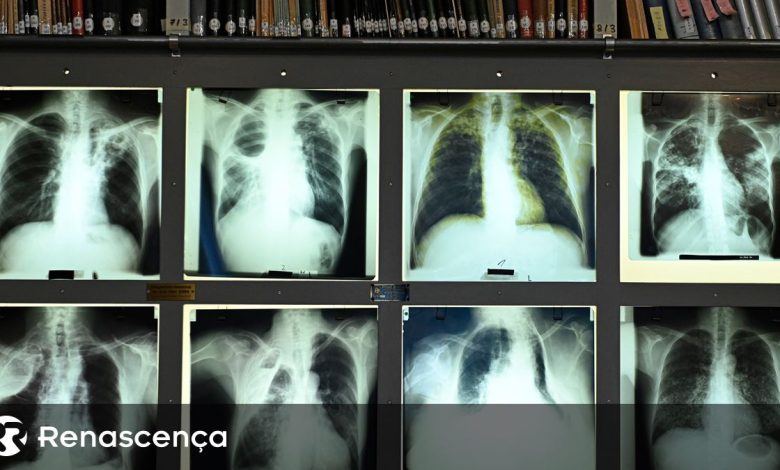

A autoridade de saúde explica que o rastreio começa por excluir doença ativa, através de sintomas e radiografia do tórax, e prossegue com um teste sanguíneo (IGRA) que avalia se houve contacto prévio com a bactéria.